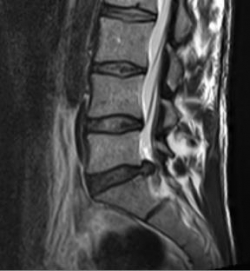

In the case of a herniated disc, the disc nucleus emerges through the ruptured disc ring. If this gelatinous core shifts backwards into the spinal canal, the nerve root located there may be displaced. The affected person feels this pressure as pain in the nerve supply area. For example, there may be pain in the buttocks or calf (herniated disc in the lumbar spine) or pain or tingling in the arm or fingers (herniated disc in the cervical spine). Most herniated discs can be treated without surgery. As a rule, the symptoms are almost completely gone after 12 weeks at the latest. However, if there is no pain relief after several months despite good conservative therapy, microsurgical removal of the herniated disc can bring about rapid relief of symptoms.

MRI with lateral reconstruction of the lumbar spine. In the area of the lowest intervertebral disc, a protrusion of the intervertebral disc to the right (back) can be seen